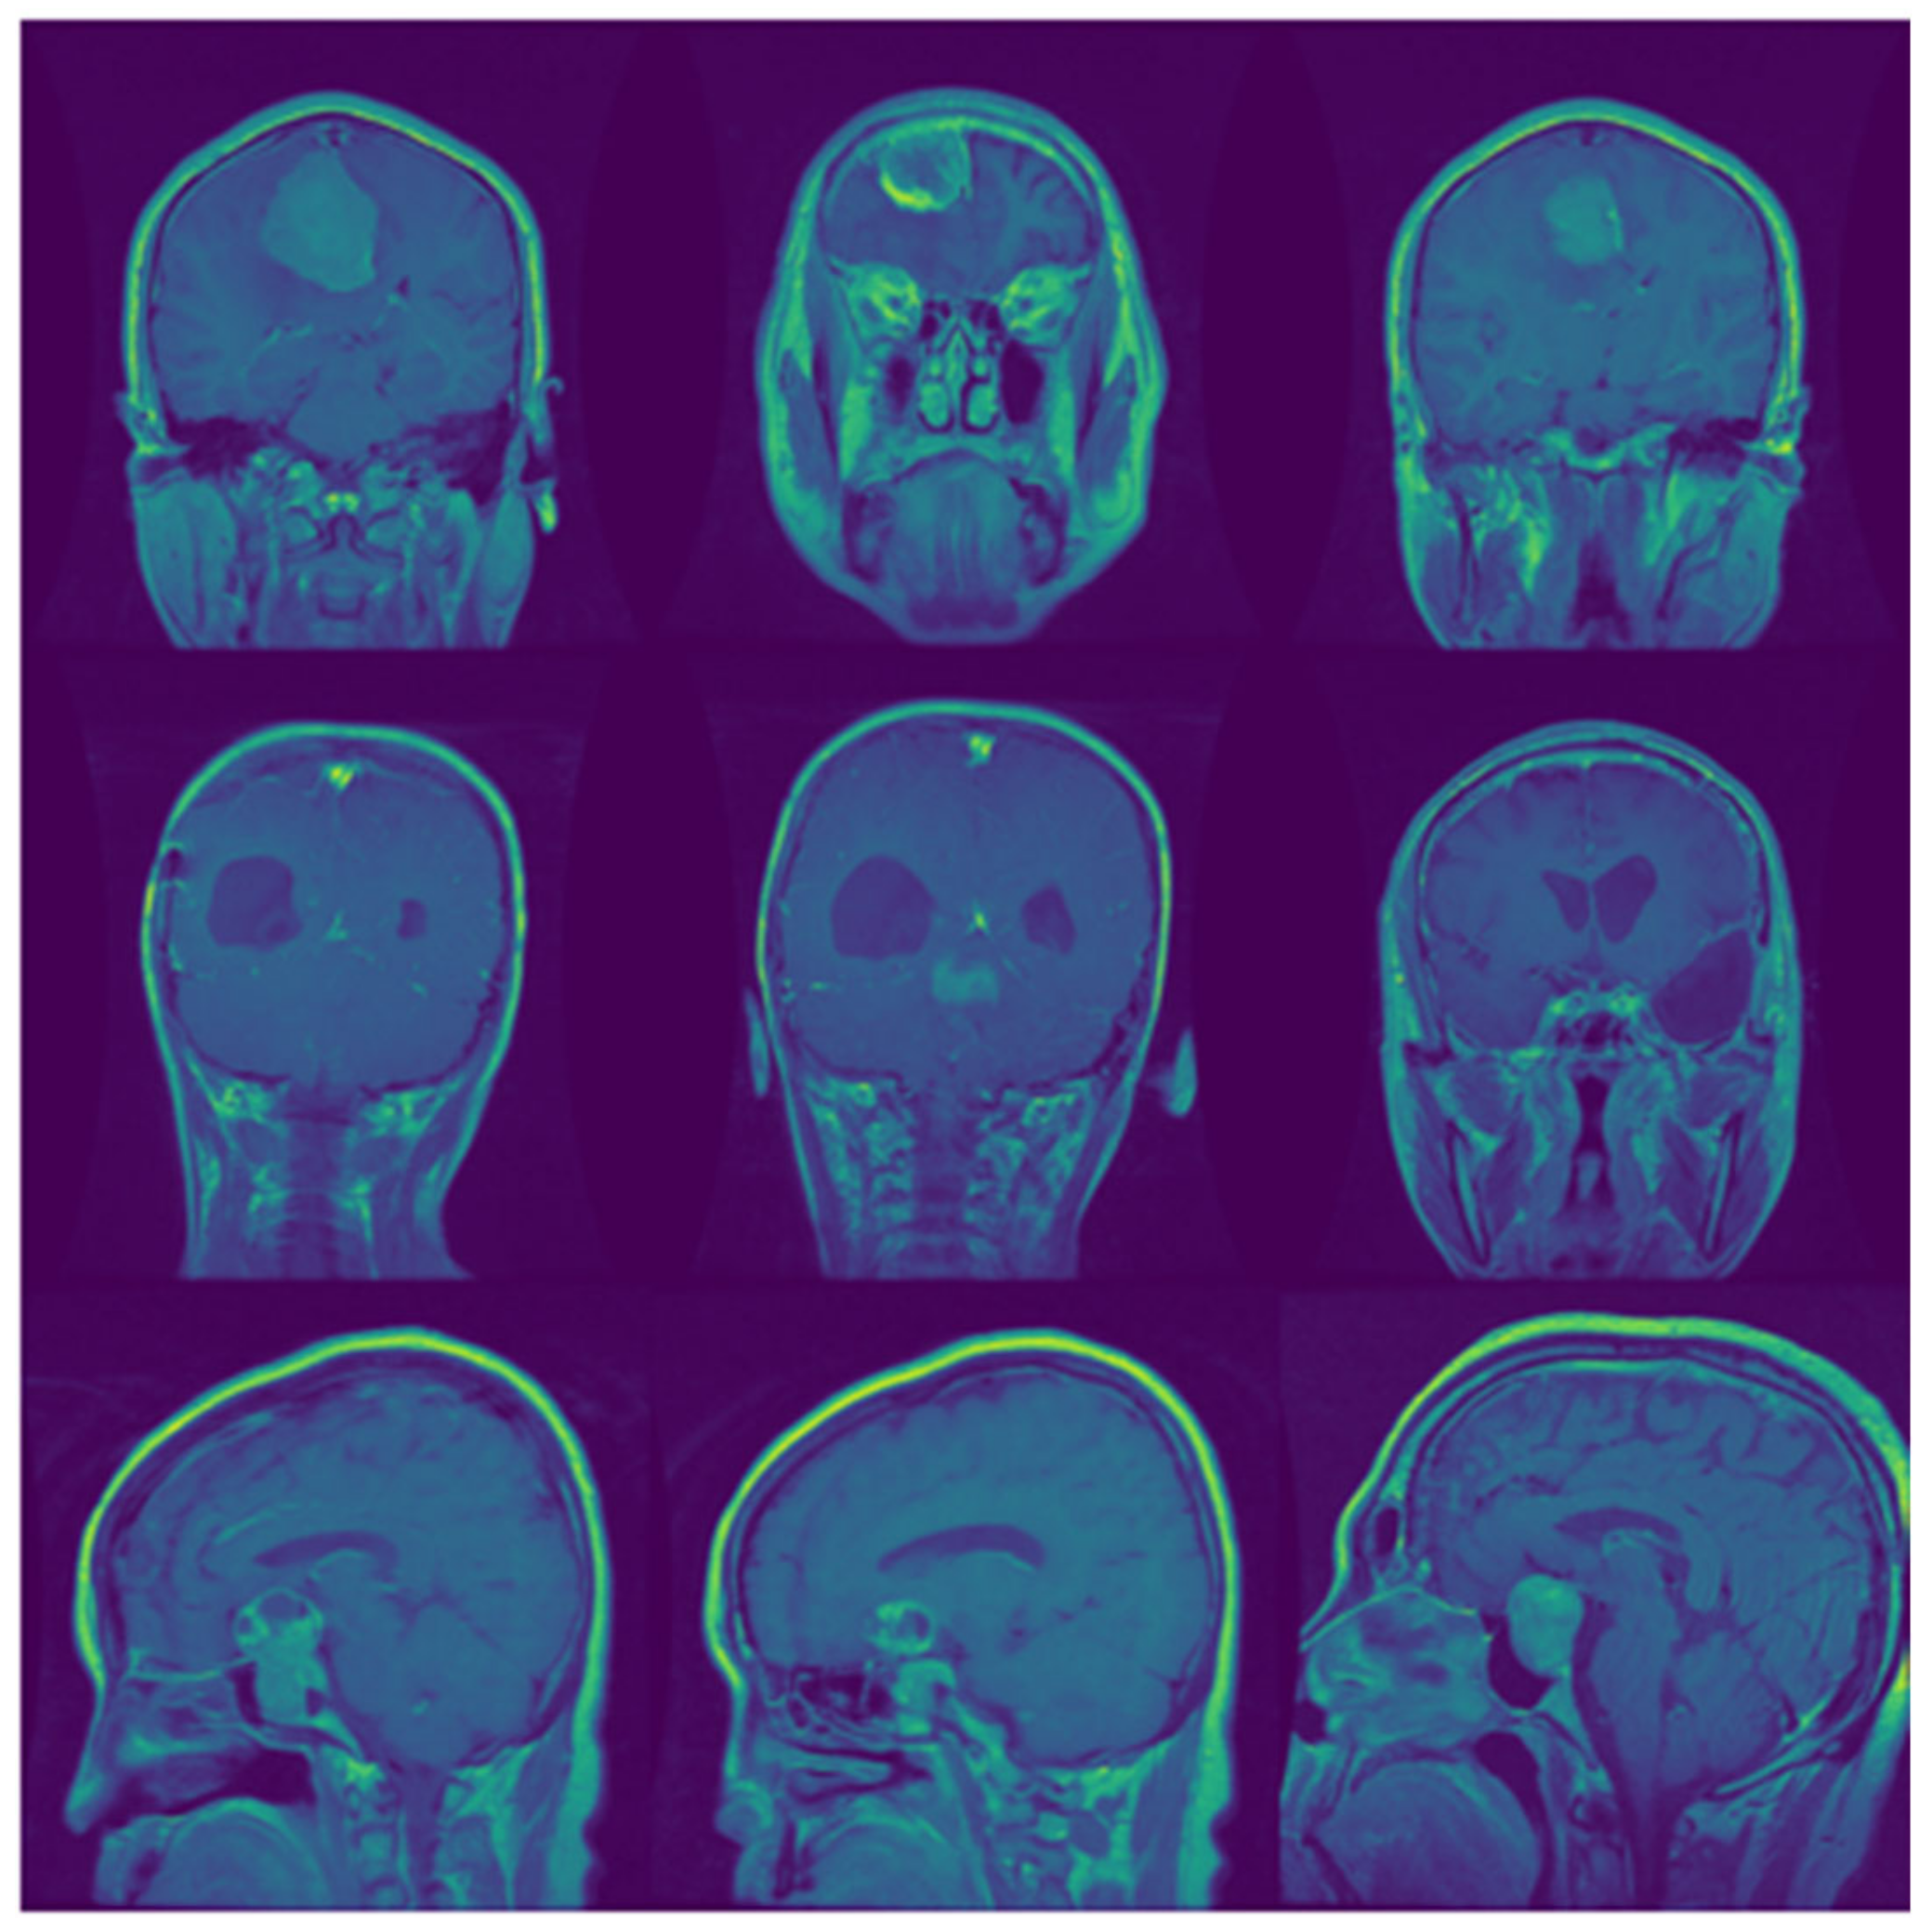

GAN-based generative models can easily learn the outer features, such as the shape of the skull, but it is quite challenging to generate fine features by using GAN, such as tumors inside the skull. We can observe this situation in Figure 6B. This Figure is taken from [29], where they used the GAN for the pre-training of brain tumor classifier and achieved an average accuracy of around 95%. Figure 6A represents the images generated by the proposed ED-GAN. Here, we can clearly observe the quality difference of generated images of brain tumors. Our proposed extension of GAN, ED-GAN, could generate better images because it samples the noise from the informative noise vector instead of random Gaussian noise. Furthermore, this is the quality of generated images that ensured the proposed framework achieved a better average accuracy of 96.25% on the test set.

Figure 6. Artificially generated brain tumor MR images. (A) MR images of brain tumor generated by proposed ED-GAN. The top and the bottom rows represent the images generated by the proposed method after 100 and 20,000 training steps, respectively. (B) Brain tumor images generated by Ghassemi et al. [29]. They used the same public dataset as ours for the training of their proposed generative model. They reported an average accuracy of around 95%, only 2% less than we achieved in this study. However, there is much quality difference in the generated images of both methods.